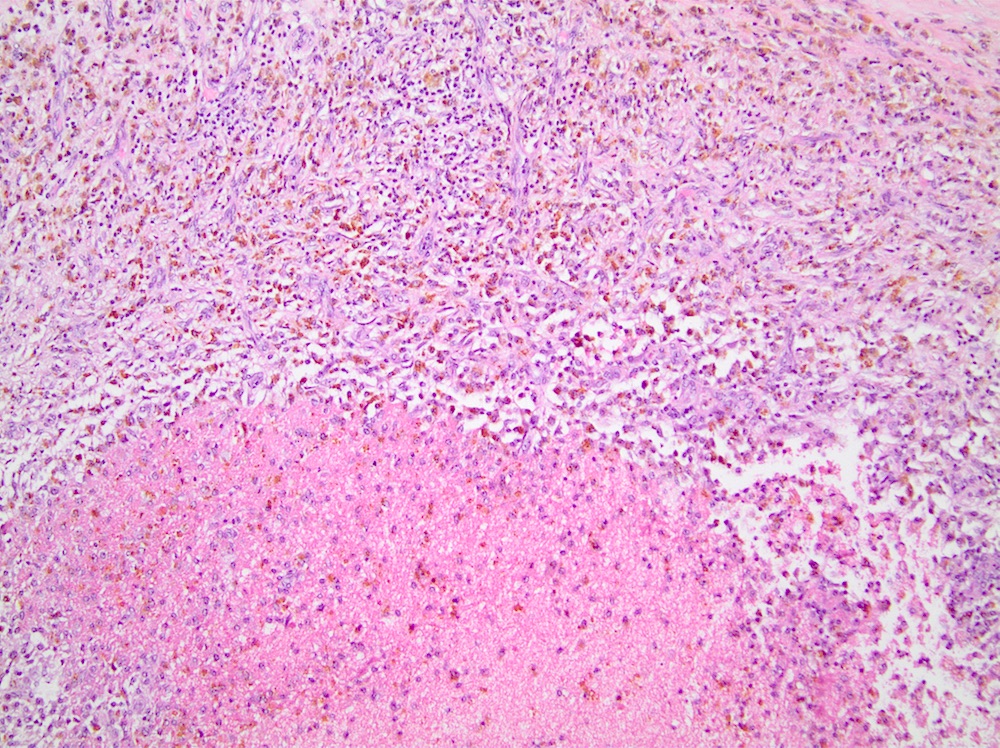

• Intermediate stage:

• Mixed inflammatory cell infiltrate of histiocytes, lymphocytes, plasma cells, sometimes with eosinophils

• Lipid laden foamy histiocytes and multinucleated foreign body type giant cells are due to phagocytosis of necrotic adipocytes

• Hemosiderin deposition

• Early fibrosis with hypercellular areas of fibroblastic proliferation

Hemorrhage and hemosiderin

Hemosiderin and giant cells

Lipid laden histiocytes and hemorrhage